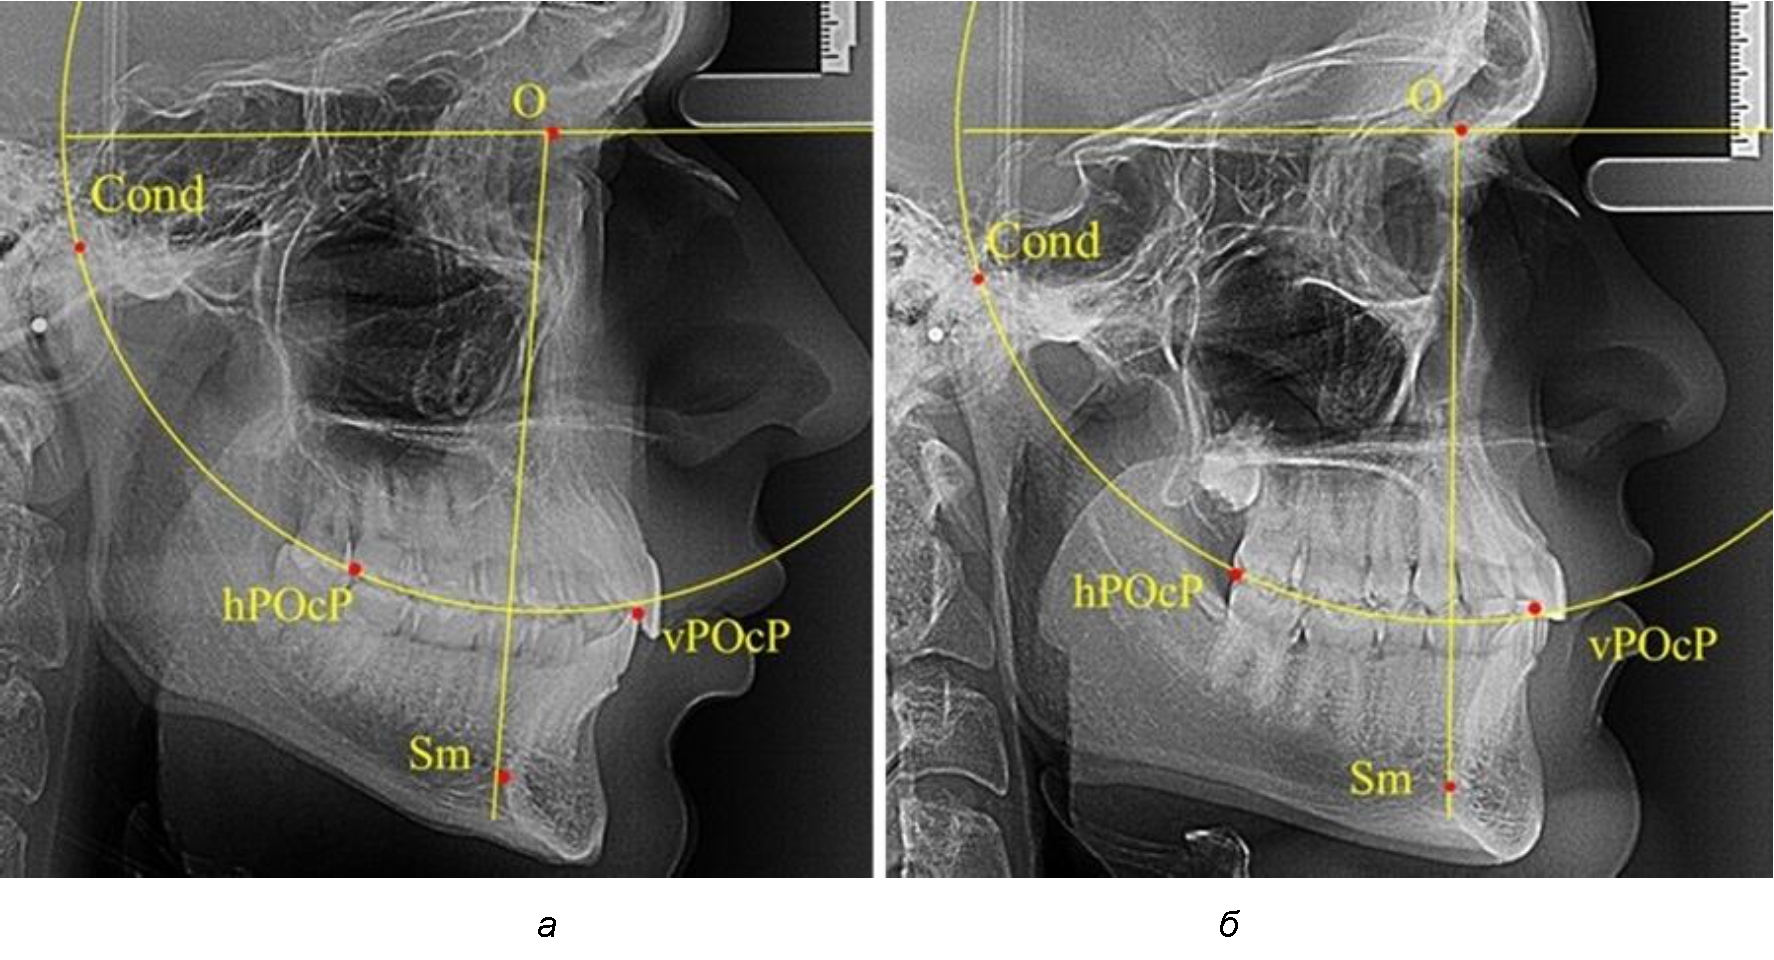

Анализ снимков проводили с использованием традиционного построения стресс-оси по Bimler. Для удобства построения использовали компьютерную программу PowerPoint. Основными точками для построения круга были передняя (vPOcP) и дистальная (hPOcP) окклюзионные точки, а также верхняя выпуклость суставной головки (Cond).

Вставка из программы в виде овала накладывалась на фотографию рентгенограммы и ручным способом растягивалась так, чтобы получился круг, проходящий через обозначенные реперные точки.

Центр окружности О, соединяющей точку резцового перекрытия с жевательной поверхностью зубов и серединой суставных головок, соединяли с выступающей точкой Sm на внутреннем контуре подбородка (рис. 1).

Рис. 1. Метод анализа ТРГ по Bimler

В норме, по резульатам исследования автора, линия Bimler проходила по вертикальной оси первых премоляров, что мы также расценивали как оптимальное их расположение.

Результаты исследования рентгенограмм с мезотрузионным типом резцов показали, что линия Bimler проходила позади первых премоляров у людей с широким типом подбородочного выступа, однако окклюзия была физиологической и не требовала удаления премоляров, что носило рекомендательный характер при проведении подобных исследований при аномалиях прикуса. У людей со средними формами подбородочного выступа линия Bimler проходила впереди первых премоляров (рис. 2).

Аналогичная ситуация была у людей и с узкими вариантами подбородочного выступа.

Таким образом, при мезотрузионном типе зубочелюстных дуг расположение премоляра впереди линии Bimler при широких вариантах подбородка не может быть критерием выбора экстракционных методов лечения.

Рис. 2. Положение первых верхних премоляров при мезотрузии с широкими (а) и средними (б) размерами подбородка